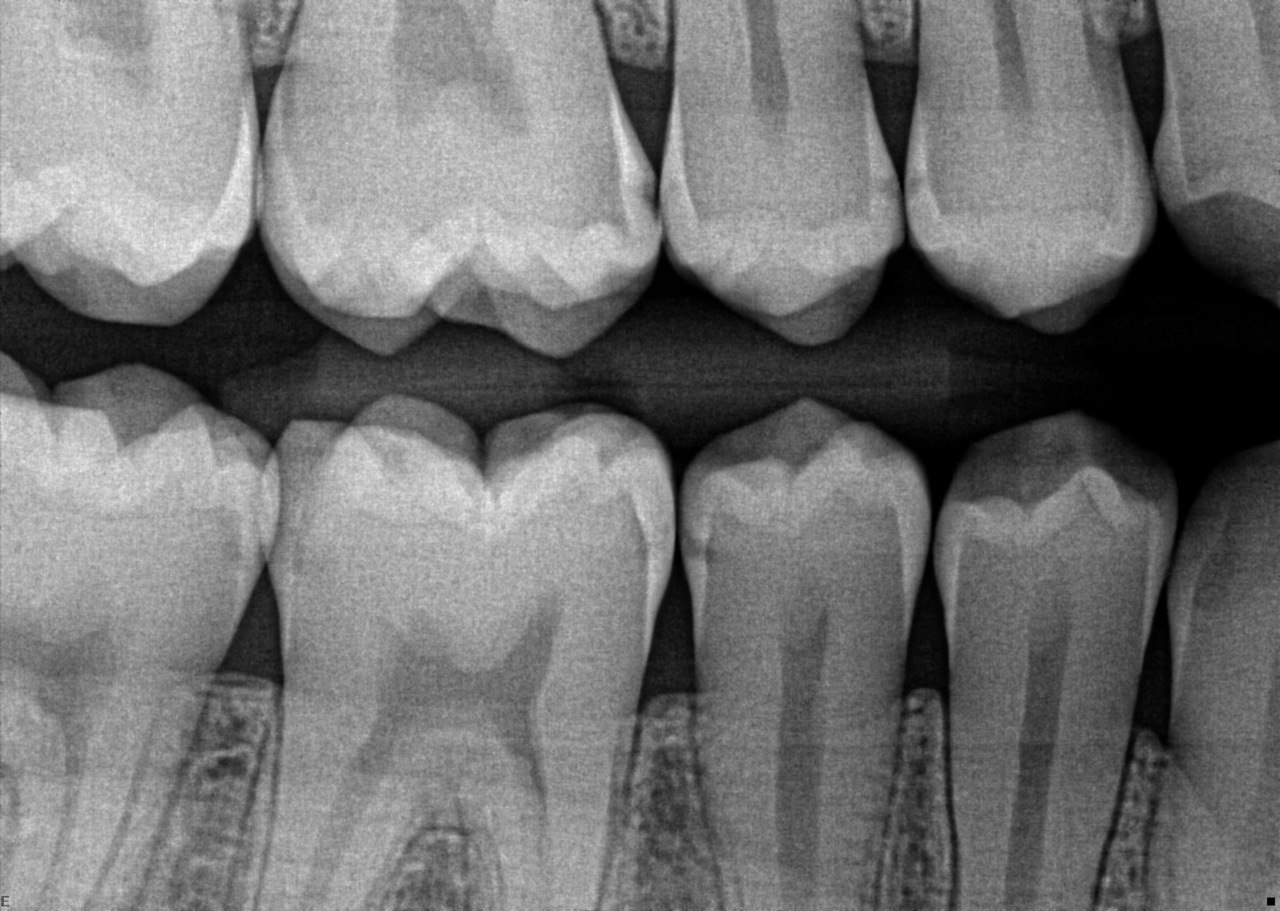

4. What surface require restoration?